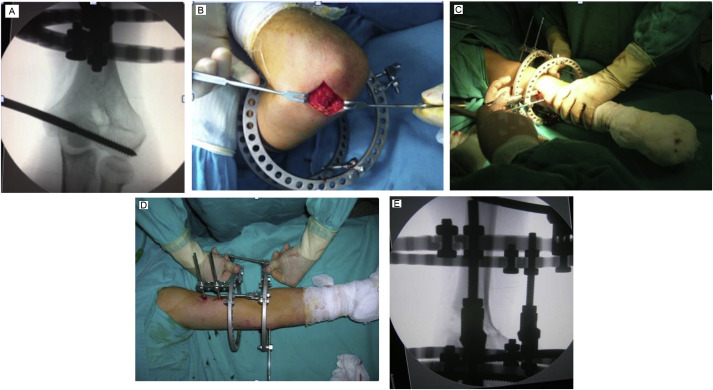

All operations were done in supine position with arm on radiolucent table under general anesthesia and without tourniquet application. Ilizarov frame assembly consisted of 2 full rings. Distal ring was positioned at level of epicondyle and proximal ring was located above level of olecranon fossa. The 2 rings were angulated at predetermined angle and were connected by 2 parallel hinges located at apex of deformity on either side of distal humeral cortex or farther in a distractive position to allow open wedge correction. Oblique plane deformity planning was conducted for 1 patient with accompanying posterior angulation. K-wires and Schanz screws were placed parallel to distal ring and elbow joint from medial and lateral epicondylar area, aligned in approximately 30° angle to each other. Ulnar nerve was protected from iatrogenic damage with use of mini-incision. Offset Schanz screws were placed on proximal ring from anteromedial and anterolateral cortex above level of radial nerve. An additional proximal half-ring was used in 3 patients to support the system. Short, oblique osteotomy proximal to olecranon fossa was performed with stab incision using multiple drilling technique. Contralateral cortex was left intact. Opening of osteotomy site and future correction were checked intraoperatively under fluoroscopy. System was locked, and active and passive elbow ROM exercises were allowed in early postoperative period (Fig. 1 ).

|

Fig. 1. Surgical technique (a) Placement of distal reference Schanz pin. (b) Medial incision to protect ulnar nerve. (c) Performing percutaneous osteotomy. (d) Clinical and (e) radiological confirmation of correction after osteotomy. |